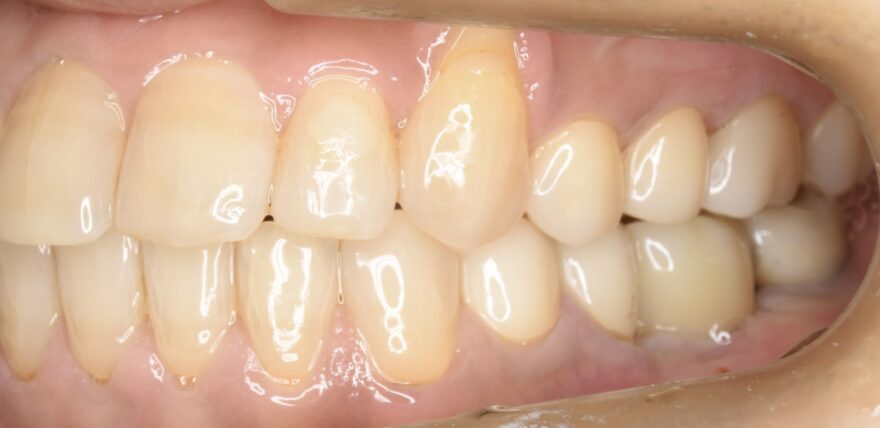

治療後の口腔内写真

なお前歯には、後戻り防止のためのワイヤーを装着しています。

右下の奥歯を失い、噛み合わせが歪んでいることが分かります。